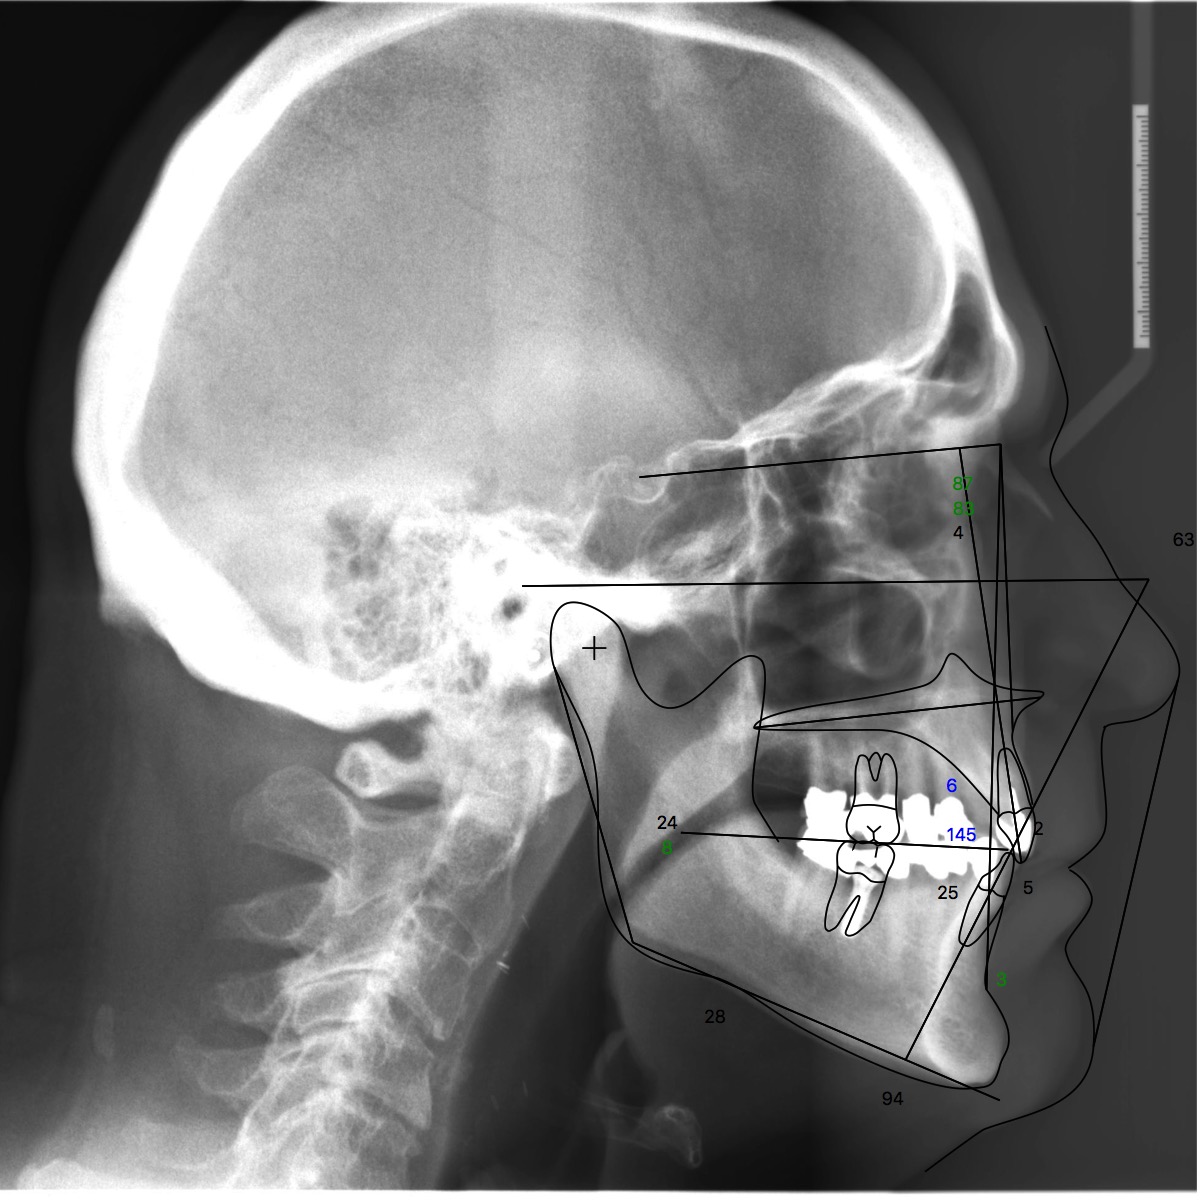

A 76-year-old, retired businessman presented to the office to improve his smile and overall oral health (Figure 1). An esthetic assessment revealed minimal display of the upper anterior teeth and dark discoloration of all teeth (Figure 2). Cephalometric analysis determined that the ANB measurement was 4°, indicating a mild Class II skeletal pattern with upright and retroclined incisors. At 145°, the interincisal angle was excessive, and at 6°, the 1-NA measurement was less than ideal (ie, 22°). If the root angulation of the upper incisors could be shifted toward the palate, it would improve the display and function of the upper anterior teeth with less restrictive anterior guidance (Figure 3).

(3.) Pretreatment cephalometric analysis.

Figure 3